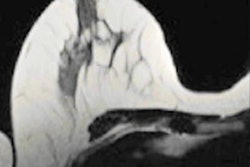

Contrast-enhanced mammography (CEM) and contrast-enhanced MRI (CE-MRI) show comparable performance when it comes to identifying breast cancer, but CE-MRI is more sensitive, a study published on 7 June in Radiology has found.

Mammography is the go-to modality for breast cancer screening, but it has sensitivity limitations in dense tissue. Digital breast tomosynthesis (DBT) and ultrasound are useful adjunct breast screening modalities, but breast MRI -- particularly contrast-enhanced exams -- is the most sensitive imaging tool for women with dense tissue, the authors explained.

The problem is that, compared with mammography, CE-MRI is less available, more expensive, and bothersome for claustrophobic patients. Contrast mammography may be readily available, but it also has disadvantages such as radiation exposure, the need for compression, and use of iodinated contrast agents.